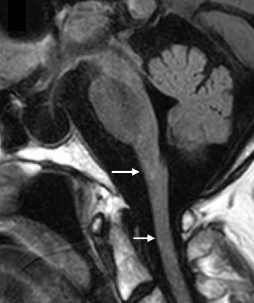

MRI findings in people with onset in adulthood are characterized by:

- Atrophy and changes in signal intensity in the cerebellum, medulla oblongata, and upper spinal cord, with variable supratentorial periventricular white matter abnormalities4

- A pattern of prominent atrophy involving the medulla oblongata and cervical spinal cord with sparing of the lower pons (ie, “tadpole sign”)8,53